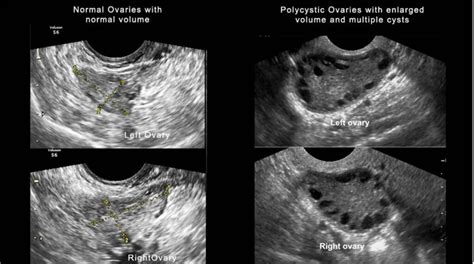

- Ovare polichistice la ecografie: Ovare mărite, cu mai mult de 12 microchisturi la suprafață.